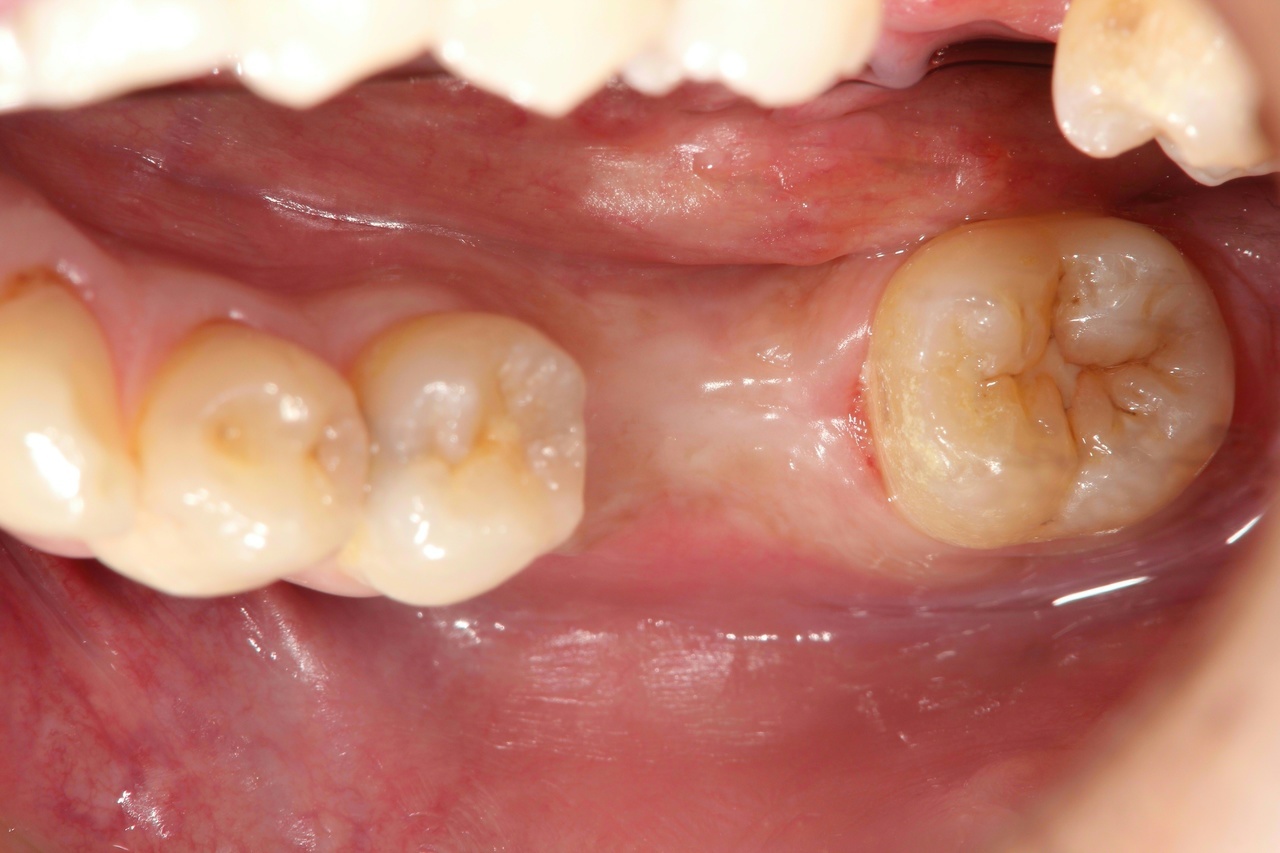

奥歯インプラント(スクリュー固定)

(伊東市 女性)

治療の流れ

むし歯で歯を失ってしまいました。

インプラントを埋入し、最終的な被せ物を装着しました。(ネジ穴をふさぐ前)

ネジ穴をふさぐとこの様な状態になります。

インプラント手術:250,000円

静脈内鎮静法:0円

既製アバットメント:90,000円

メタルボンド:130,000円

総額:470,000円+税